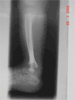

Pre Op

X-Rays